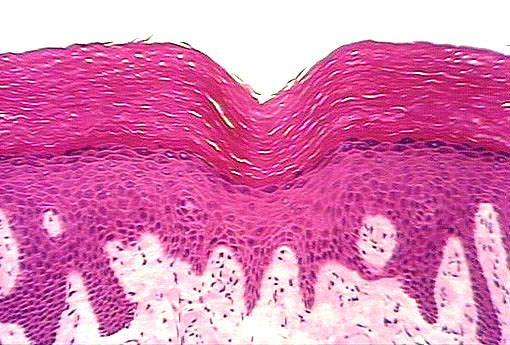

Thick skin

1. Lined by stratified squamous epithelium.

2. Presence of keratin layer.

3. Epidermal projections into dermis are epidermal papillae.

4. Dermal projections into epidermis are dermal papillae.